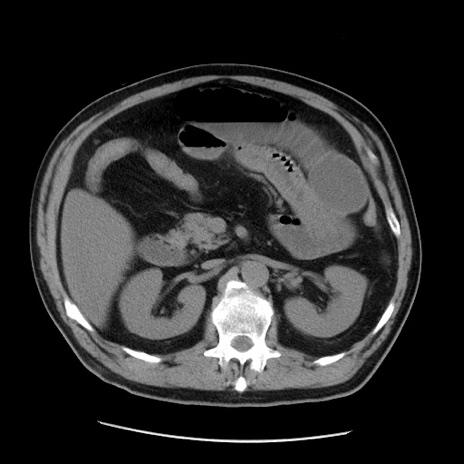

症例20(横断像)

【症例】 60歳代男性

【主訴】 腹部膨満、嘔吐

【現病歴】5日前頃より倦怠感を認め食事量減少し4日前の朝嘔吐、食事摂取困難となった。 3日前近医受診し点滴施行され整腸剤などを処方された。 当日他院を受診し、腹部膨満著明、炎症反応の上昇(CRP10.8、WBC11200)あり、紹介受診となる。

【身体所見】 意識JCS1 受け答えがはっきりしないBP 111/57mHg、 P 67bpm、、BT35.2°C、SpO2 97%(RA)、 腹部:膨隆、打診で鼓音あり、全体的に圧痛有り、腸蠕動音(-)、反跳痛ははっきりせず。

【データ】WBC 11400、CRP 14.20